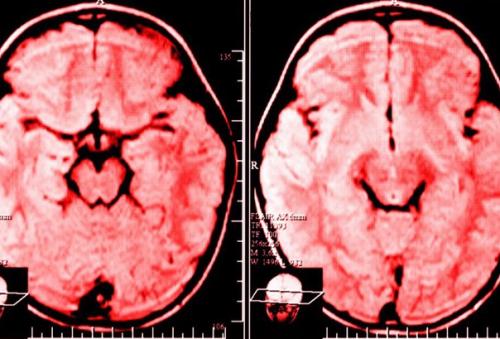

Сфера визуализации головного мозга и нейробиологии далеко шагнула вперед за последние 20 лет, что дает нам полную уверенность говорить о том, что мозг обладает способностью перестраиваться, а мы все - инженеры своего мозга.

Нейропластичность мозга - профессиональный термин, описывающий длительные изменения в мозге на протяжении всей жизни человека. И это замечательная вещь.